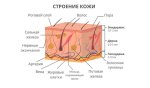

Пиздец, какая микрофлора кишечника, какая кровь нахуй. Анон, ты хотя бы фак читал? Тебя наебали, а ты и сам обманываться рад. Чаще всего прыщи ничего общего не имеют с проблемами кишечника, и «внутренняя проблема» заключается в генетической предрасположенности к неадекватной работе сальных желёз, из-за малейших/рандомных триггеров сальные железы начинают вырабатывать очень много сала, вызывая закупорку пор, тогда внутри кожи начинают размножаться бактерии акне(так и называются Cutibacterium acnes), развивается воспаление, опять же из-за закупорки пор, и мы получаем прыщи и чёрные точки. Всё. Более прошаренные аноны, поправьте, если где-то сказал не так.

Пиздец, какая микрофлора кишечника, какая кровь нахуй. Анон, ты хотя бы фак читал? Тебя наебали, а ты и сам обманываться рад. Чаще всего прыщи ничего общего не имеют с проблемами кишечника, и «внутренняя проблема» заключается в генетической предрасположенности к неадекватной работе сальных желёз, из-за малейших/рандомных триггеров сальные железы начинают вырабатывать очень много сала, вызывая закупорку пор, тогда внутри кожи начинают размножаться бактерии акне(так и называются Cutibacterium acnes), развивается воспаление, опять же из-за закупорки пор, и мы получаем прыщи и чёрные точки. Всё. Более прошаренные аноны, поправьте, если где-то сказал не так.